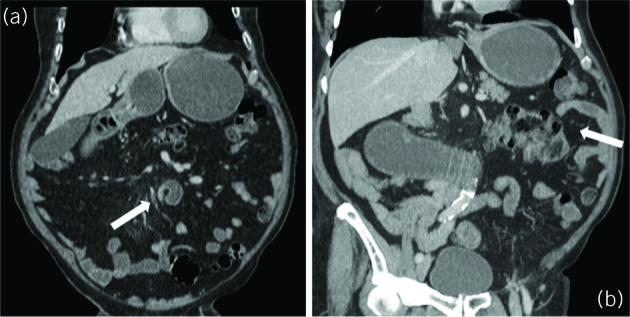

Figure 1.

Computed tomography of the abdomen and pelvis with intravenous contrast; coronal view. (A) A smooth narrowing and ‘beaking’ of the distal duodenum is seen at D3/D4 (arrow) with no obvious mass. There is dilation of the stomach. (B) There is distention of the stomach and visualised section of the duodenum. The small bowel loops are predominantly on the right, and the caecum and ileocaecal valve (arrow) is located in the left upper quadrant.

Computed tomography (CT) with intravenous contrast showed dilatation of the distal oesophagus, stomach and duodenum, and a cutoff point at the third/fourth part of the duodenum with a twist in the small bowel mesentery (Fig 1A). The terminal ileum and caecum were located in the left upper quadrant (Fig 1B). An oesophagogastroduodenoscopy was attempted, but the scope was unable to pass the point of obstruction at D3.